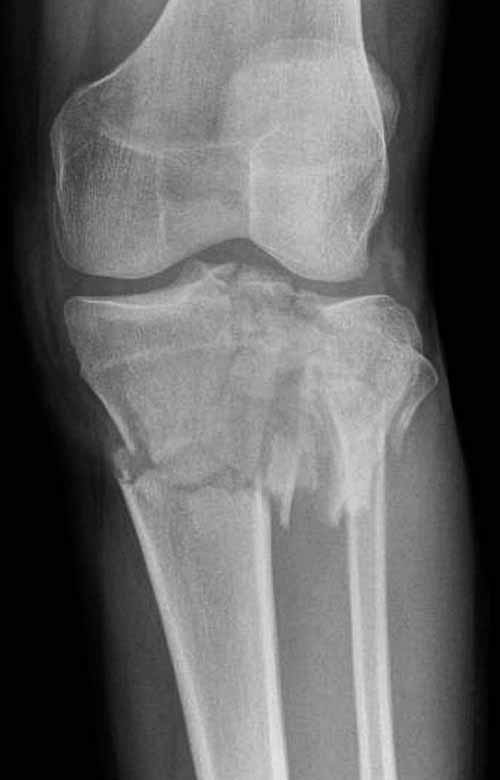

Двухколоннный перелом тибиал плато с вовлечением проксимального диафиза. Внутрисуставной компонент без смещения, и такой перелом можно лечить любым из описанных методов, о которых говорят наши коллеги.

Как понял, аппарат Илизарова не рассматривается предпочтительным для фиксации методом, хотя на фоне отека было бы идеальным для данного перелома. Для пластины требуется идеальная кожа, иначе наличие “суперсовременных имплантов” не поможет, и могут развиться серьезные осложнения.

Частая ошибка, когда фиксацию двух колонного перелома проводят одиночной пластиной, т.е с одной стороны, и такая фиксация не удерживает, происходит вторичноое смещение. Необходимо нейтрализовать второй пластиной или дополнительным наружным фиксатором.

Кстати, коллеги правы для уточнения характера перелома надо делать Компьютерную Томографию.